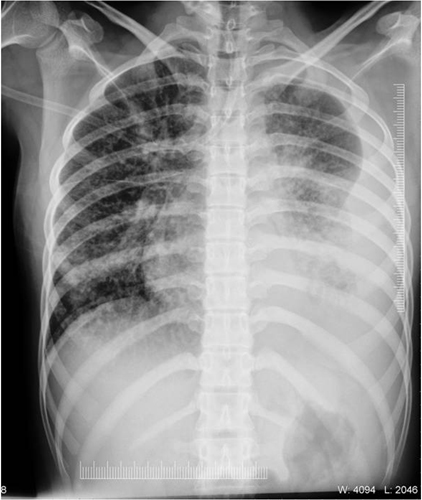

A 24-year-old female previously diagnosed to have SLE with Class IV Lupus Nephritis one year back based upon American College of Rheumatology (ACR) criteria [9] on immunosuppressive therapy with corticosteroids and mycophenolate mofetil presented with history of cough with expectoration for two weeks associated with fever for the same duration. She had history of contact with a case of TB in her household. On evaluation she was febrile (Temperature: 101°F) with a blood pressure of 100/70 mmHg and pulse rate of 80/min and respiratory rate of 22/min. She maintained her oxygen saturation at room air. She had pallor and bilateral ankle oedema. Her systemic examination was within normal limits. Her investigations showed haemoglobin of 8.2 gm%, Total Leucocyte Count (TLC) of 9600/mm3 (65% neutrophils, 30% lymphocytes and 5% monocytes), platelet count of 1.5 lakhs/mm3 and an Erythrocyte Sedimentation Rate (ESR) of 73 mm/hr. Her renal function tests were deranged with a serum urea and creatinine of 74 mg/dl and 1.8 mg/dl respectively. Serum Albumin Levels and Total Protein Levels were low (1.6 gm/L and 3.8 gm/L) respectively. Rest of her liver functions, coagulogram, serum electrolytes were normal. Her chest X-ray showed bilateral patchy infiltrates with a left sided pleural effusion [Table/Fig-1]. Her sputum was positive for Acid Fast Bacilli (AFB) (2+). Her pleural fluid analysis showed an exudative fluid with predominantly lymphocytic cells with an increased Adenosine Deaminase Level (42 IU/l). She was diagnosed as SLE with sputum positive pulmonary TB with tubercular pleural effusion and started on anti-tubercular therapy with Category 1 Directly Observed Treatment Short course (DOTS) including isoniazid, rifampicin, ethambutol and pyrazinamide. She was followed-up and was found to have responded well to therapy. Her sputum was negative for AFB at the end of two months of therapy with complete resolution of infiltrates and effusion on chest X-ray.

Chest X-ray showing bilateral patchy infiltrates with a left sided pleural effusion.